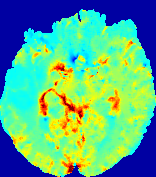

LesionRefer to captionRefer to captionRefer to captionRefer to captionRefer to captionRefer to caption𝐕rgbsubscript𝐕𝑟𝑔𝑏{\bf{V}}_{rgb}Refer to captionRefer to captionRefer to captionRefer to captionRefer to captionRefer to caption𝐕2subscriptnorm𝐕2{\|\bf{V}}\|_{2}Refer to captionRefer to captionRefer to captionRefer to captionRefer to captionRefer to captionRefer to caption3.53.53.52.82.82.82.12.12.11.41.41.40.70.70.70.00.00.0(mm/s)𝑚𝑚𝑠(mm/s)D𝐷DRefer to captionRefer to captionRefer to captionRefer to captionRefer to captionRefer to captionRefer to caption0.0200.0200.0200.0160.0160.0160.0120.0120.0120.0080.0080.0080.0040.0040.0040.0000.0000.000(mm2/s)𝑚superscript𝑚2𝑠(mm^{2}/s)Slice #1Slice #2Slice #3Slice #4Slice #5Slice #6

Figure 4: PIANO feature maps for another patient in the ISLES 2017 training set, where the lesion is located in the right hemisphere. Top row: segmented stroke lesion region (white) on different slices. The corresponding slices for the PIANO feature maps are shown in the following rows.

For a better insight into an estimated velocity field 𝐕𝐕{\bf{V}} and diffusion field 𝐃𝐃{\bf{D}}, we compute the following maps: (1) 𝐕rgbsubscript𝐕𝑟𝑔𝑏{\bf{V}}_{rgb}: Color-coded orientation map of 𝐕=(Vx,Vy,Vz)T𝐕superscriptsuperscript𝑉𝑥superscript𝑉𝑦superscript𝑉𝑧𝑇{\bf{V}}=(V^{x},V^{y},V^{z})^{T}, obtained by normalizing 𝐕𝐕{\bf{V}} to unit length and mapping its 3 components to red, green, blue respectively; (2) 𝐕2subscriptnorm𝐕2\|{\bf{V}}\|_{2}: 222 norm of 𝐕𝐕{\bf{V}}; (3) D𝐷D: scalar field in Eq. 5.

Fig. 3 and Fig. 4 show the PIANO feature maps estimated from two ISLES 2017 patients: all are highly consistent with the lesion in both cases. Details of the blood flow trajectories are revealed in 𝐕rgbsubscript𝐕𝑟𝑔𝑏{\bf{V}}_{rgb} by the ridged patterns and the sharp changes of colors in the unaffected (right) hemisphere, while the flat patterns appearing within the lesion provide little directional information about the velocity and indicate low velocity magnitudes. Velocity magnitudes are more directly visualized via 𝐕2subscriptnorm𝐕2\|{\bf{V}}\|_{2}, from which one can easily locate the lesion where 𝐕2subscriptnorm𝐕2\|{\bf{V}}\|_{2} is low. D𝐷D also indicates lower diffusion values in the lesion, though with less contrast potentially due to the fact that it captures the accumulated effect of CA diffusion at the voxel-level.